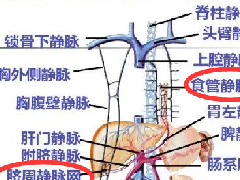

大范围的冠状位增强序列有助于对血管、胆管、十二指肠区域以及周围受累情况的评估,